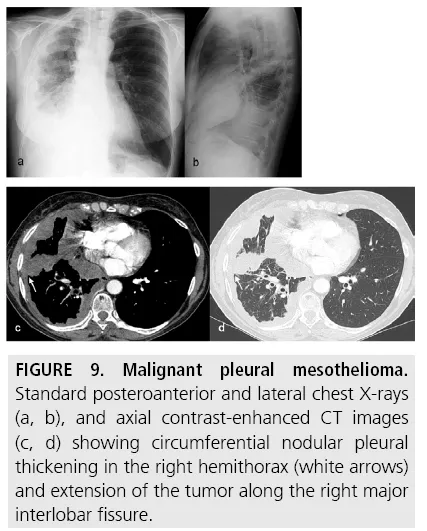

- Mesothelioma: Pleural malignancy.

- 📌 Risk: Asbestos exposure (primary).

- Imaging: Unilateral effusion, rind-like pleural thickening.

⭐ Strongly linked to occupational asbestos exposure; long latency (20-40 yrs).

- Mesothelioma is strongly associated with asbestos exposure; presents with pleural thickening/effusion.